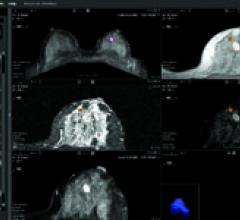

CADstream solutions provide fast, easy and reliable analysis and interpretation of breast and prostate MRI studies. At RSNA, Merge Healthcare will show works-in-progress for its newest CADstream application designed specifically for liver MRI studies.